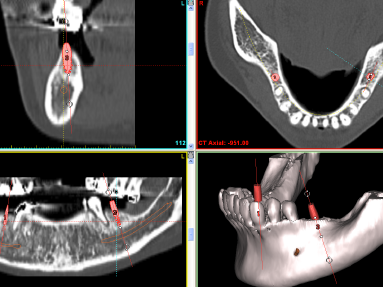

パノラマ撮影だけでなく顎の骨の厚みや形態、根の3次元的な形態を知りたいときは、断層撮影も可能です。これは平面的な像より多くの情報が獲得できます。

CT撮影

インプラントの安全なオペにはCT撮影が必要です。神経や骨などを三次元的に把握することができるからです。当クリニックでは可能なかぎり立体的な分析が必要なケースではCT撮影をするようにしております。(撮影はESTクリニックに依頼)

OP300

歯科用CTと言われている3Dレントゲン撮影機能を搭載したパノーラ19を使用しておりましたがこのほどOP300を新しく導入いたしました.これによりいままで病院に外注していた多数歯の症例も撮影可能になり解像度も飛躍的に向上しました.また3Dの画像も飛躍的に向上したため 患者さんによりわかりやすく説明することができます.